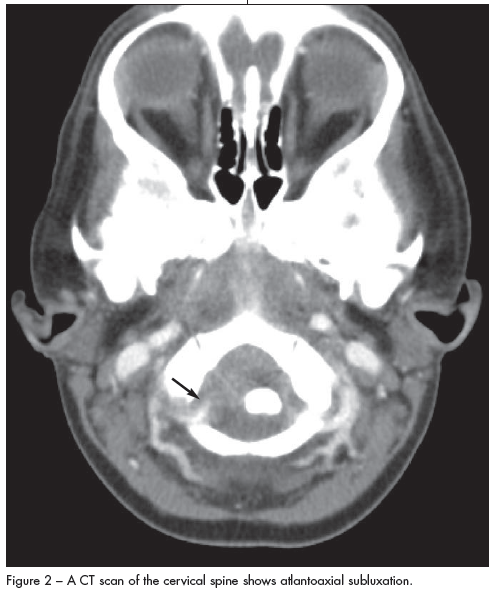

Archana Chatterjee, MD, PhD; Ashlea Franques, MD; Meera Varman, MD; Amy Holst, MD; John Treves, MD

Grisel syndrome should be considered in patients who present with new-onset torticollis that is painful or resistant to manipulation.